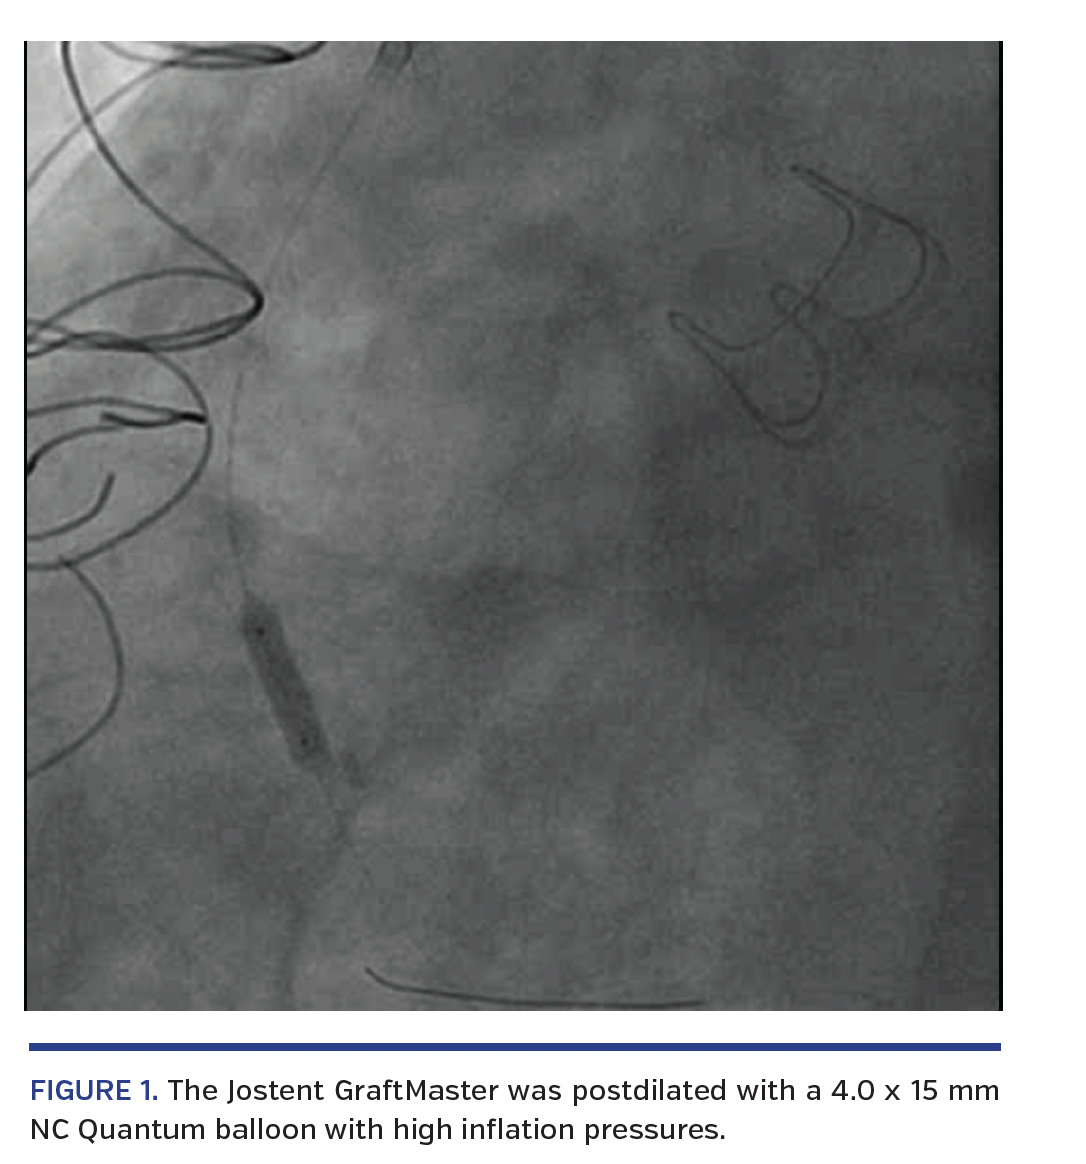

The patient was electively admitted to the catheterization lab. Bilateral 8 Fr femoral arterial access was obtained. An 8 Fr Multipurpose guiding catheter was used to engage the SVG to RCA. A 0.014˝ Prowater guidewire was passed through the vein graft into the distal native RCA. Percutaneous coronary angioplasty was performed with a 3.0 x 15 mm Apex OTW balloon (Boston Scientific) and intracoronary stenting was performed with a 3.5 x 26 mm Jostent GraftMaster (Video 1). Postdilation was performed with a 4.0 x 15 mm NC Quantum balloon with high inflation pressures (Figure 1). IVUS post stent placement revealed good stent expansion and apposition, without edge dissection (Video 2).